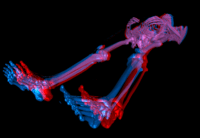

- supports stereo rendering

An anaglyph image of a human body rendered with ImageVis3D. |